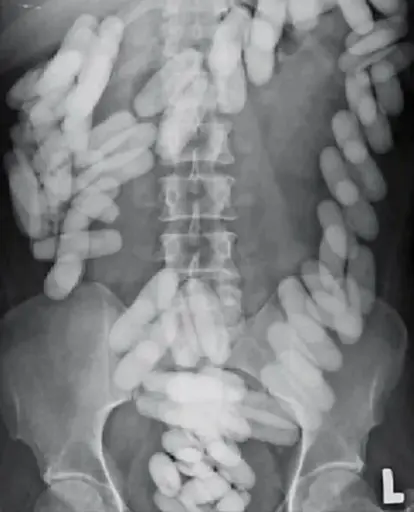

minus-squareSaveTheTuaHawk@lemmy.calinkfedilinkEnglisharrow-up7·2 months agoLab stir bars are Teflon coated and look like candy. No idea where anyone could find that many stir bars.

Lab stir bars are Teflon coated and look like candy. No idea where anyone could find that many stir bars.